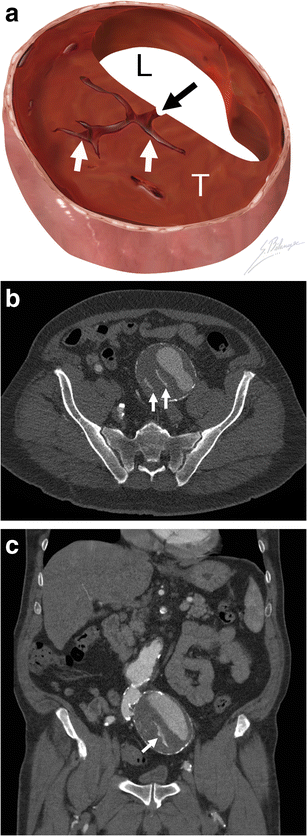

Thrombus fissuration. a Illustration demonstrates blood (black arrow) dissecting from the aortic lumen (L) into a mural thrombus (T). The infiltrating blood is seen as linear fissurations (white arrows). b Axial and c coronal enhanced CT of a 64-year-old man shows linear infiltrations of contrast material (white arrows) within the hypodense mural thrombus. The patient underwent successful emergent AAA repair before complete rupture occurred